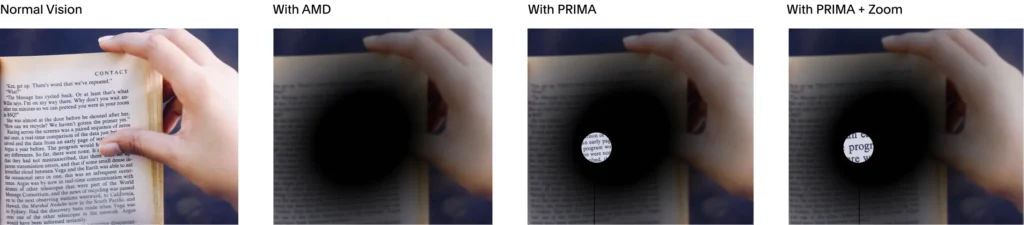

ชิป Prima ช่วยให้ผู้ป่วยตาบอดจากโรคจอประสาทตาเสื่อมตามวัยสามารถกลับมามองเห็นได้ โดยมันจะผ่าตัดวางไว้ใต้จอประสาทตาที่อยู่หลังสุดของลูกตา

บริษัท Science Corporation บริษัทพัฒนา Brain–computer interface (BCI) ได้พัฒนาชิป Prima ขึ้นมาโดยจะผ่าตัดและวางชิปตัวนี้ไว้ใต้จอประสาทตาที่อยู่หลังสุดของลูกตา เมื่อใช้งานร่วมกับกล้อง และแว่น จะช่วยให้ คนตาบอดมองเห็นดีพอที่จะสามารถอ่านหนังสือ เล่นไพ่ และไขปริศนาอักษรไขว้ได้

ชิป Prima เป็นเทคโนโลยีของบริษัท Science Corporation บริษัทพัฒนา Brain–computer interface BCI โดยมันจะผ่าตัดวางไว้ใต้จอประสาทตาที่อยู่หลังสุดของลูกตา เมื่อใช้งานร่วมกับกล้อง และแว่น จะช่วยให้ คนตาบอดมองเห็นดีพอที่จะสามารถอ่านหนังสือ เล่นไพ่ และไขปริศนาอักษรไขว้ได้

ชิป Prima ประกอบด้วยชิปสี่เหลี่ยมจัตุรัสขนาด 2 มม. ที่ถูกผ่าตัดวางไว้ใต้จอประสาทตา ตรงส่วนหลังสุดของลูกตา โดยใช้เวลาผ่าตัดนานถึง 80 นาที โดยจะใช้งานร่วมกับแว่นตาพร้อมกับกล้องที่จะบันทึกภาพ และส่งแสงอินฟราเรดไปยังชิป แล้วชิปดังกล่าวจะทำหน้าที่เสมือนแผงโซลาร์เซลล์ขนาดเล็ก ที่จะแปลงแสงเป็นการกระตุ้นไฟฟ้า และส่งไปยังสมอง จากนั้นสมองจะตีความสัญญาณดังกล่าวเป็นภาพ ซึ่งเป็นการเลียนแบบกระบวนการการมองเห็นตามธรรมชาติ

Prima แตกต่างจากอุปกรณ์ปลูกถ่ายจอประสาทตาอื่นๆ ตรงที่มันช่วยให้มองเห็นรูปร่าง ลวดลาย และองค์ประกอบภาพอื่นๆ ของวัตถุได้ อย่างไรก็ตาม สิ่งที่ผู้ใช้มองเห็นนั้นไม่ใช่การมองเห็นแบบ “ปกติ” :ซึ่งประการหนึ่งก็คือ ผู้ใช้จะมองไม่เห็นเป็นสี แต่จะมองเห็นเป็นภาพที่ผ่านการประมวลผลแล้วซึ่งจะเป็นสีโทนเหลือง

มีการทดลองโดยรับสมัครผู้ป่วยโรคจอประสาทตาเสื่อมตามวัย (AMD) ซึ่งทำให้สูญเสียการมองเห็นไปอย่างช้าๆ ผู้ป่วยโรคดังกล่าวยังคงมองเห็นภาพรอบข้างได้ แต่มีจุดบอดในการมองเห็นตรงกลาง ทำให้ยากต่อการอ่านหนังสือ จำใบหน้าได้ หรือมองเห็นในที่แสงน้อย